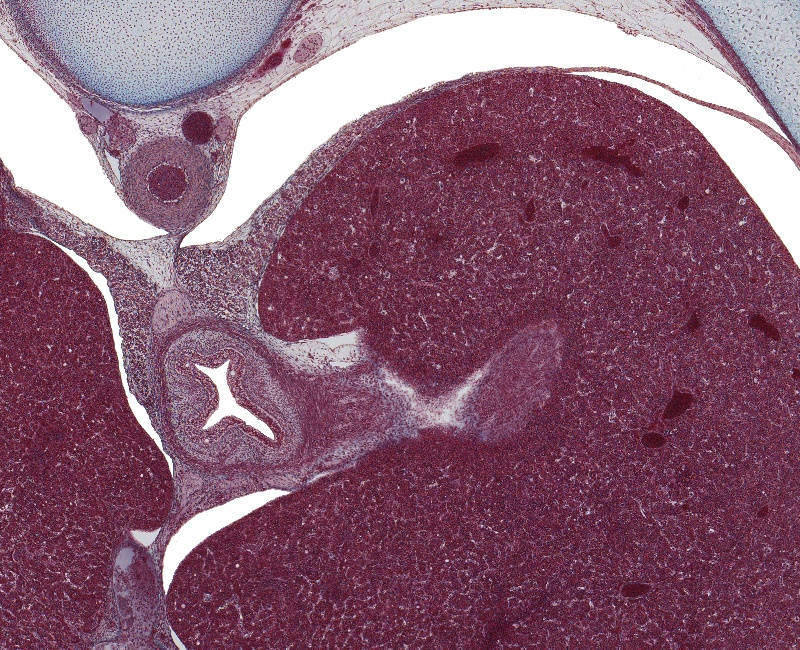

Tissue

Lower Esophagus, Liver, and Crura of Diaphragm

Carnegie Embryo #9226

149-01-01